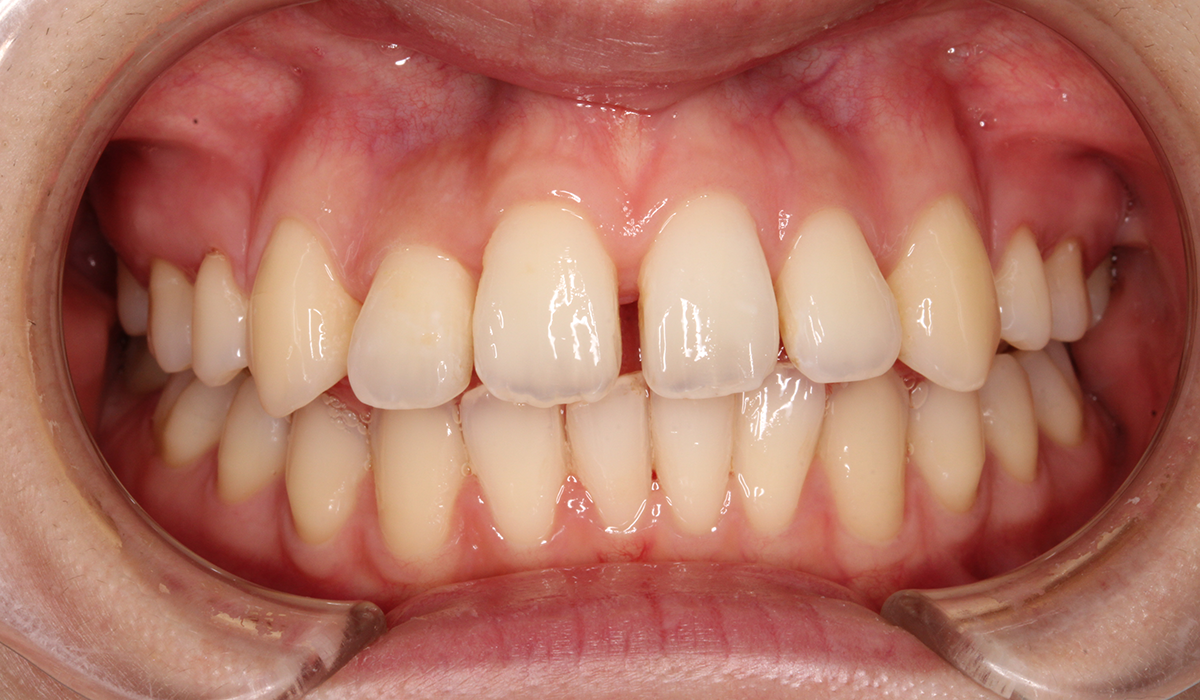

今回ご紹介する患者様は、全体的な歯のガタツキを気にされており、矯正検査後叢生Ⅰ級と診断いたしました。

正面

BK終了時

術後